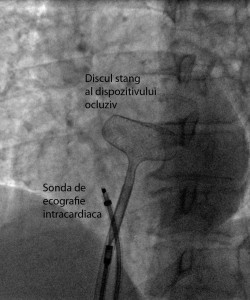

În data de 23 noiembrie 2015, în cadrul Cardiostructural Clinic din Spitalul Monza din Bucureşti au fost efectuate cu succes primele proceduri endovasculare ghidate prin ecocardiografie intracardiacă. Echipa medicală a Centrului de Intervenţii Structurale Cardiovasculare constituită din Dr Şerban Bălănescu, Dr Adrian Linte şi Dr Andrada Bogdan cu suportul tehnic al Dr Eustaquio Onorato de la Clinica Humanitas Gavazzeni, Bergamo, au realizat tratamentul endovascular cu închiderea unui defect septal atrial la o pacientă în vârstă de 49 ani şi a unui foramen ovale patent la o pacientă în vârstă de 17 ani, care a suferit un accident vascular cerebral ischemic recent.

Clasic pentru toate acestea se foloseşte ecocardiografia transesofagiană, care nu poate fi efectuată fără sedare profundă sau anestezie generală cu intubare orotraheală. Aceasta impune prezenţa în sala de cateterism a unui anestezist şi a unui ecocardiografist, medicaţie şi supraveghere complexă, precum şi îngrijirea pe termen scurt a pacientului intubat în terapia intensivă după ieşirea din sala de cateterism. Ecocardiografia intracardiacă se efectuează sub anestezie locală la pacient treaz, fără a necesita anestezist şi plasarea unei sonde de ecocardiografie în esofag. Aceste avantaje coroborate cu faptul că imaginile obţinute au o calitate superioară celor transesofagiene a făcut ca în multe săli moderne de cateterism ecocardiografia intracardiacă să înlocuiască ecocardiografia transesofagiană mai ales in cazul excluderii percutane a defectului septal atrial, a defectului septal ventricular, a foramenului ovale patent sau a puncţiei transseptale. Prin utilizarea unui sistem modern de ecocardiografie intracardiacă Cardiostructural Clinic din cadrul Spitalului Monza București, vine astfel în întâmpinarea nevoilor pacienţilor în ceea ce priveşte siguranţa şi confortul acestora precum şi îmbunătăţirea actului medical în sine. Ne propunem ca în viitor toate procedurile pe care le efectuăm pentru corecţia endovasculară a bolilor cardiace congenitale ale septului interatrial să fie realizate cu ajutorul acestei metode imagistice moderne, fiabile şi mai ales care conferă confort pacientului în timpul intervenţiilor endovasculare.

2_proteza_in_timpul_implantului